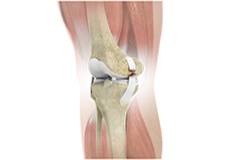

Patellofemoral Knee Replacement

The knee can be divided into three compartments: patellofemoral, the compartment in front of the knee between the kneecap and thighbone, the medial compartment, on the inside portion of the knee, and lateral compartment which is the area on the outside portion of the knee joint.

Arthritis of the knee can cause pain and stiffness, making regular activities such as walking and bending difficult. As arthritis progresses, conservative treatments tend to lose their efficacy and more definitive treatment should be considered. Knee replacement surgery involves replacing worn or damaged joints with implants to reduce pain and improve movement.